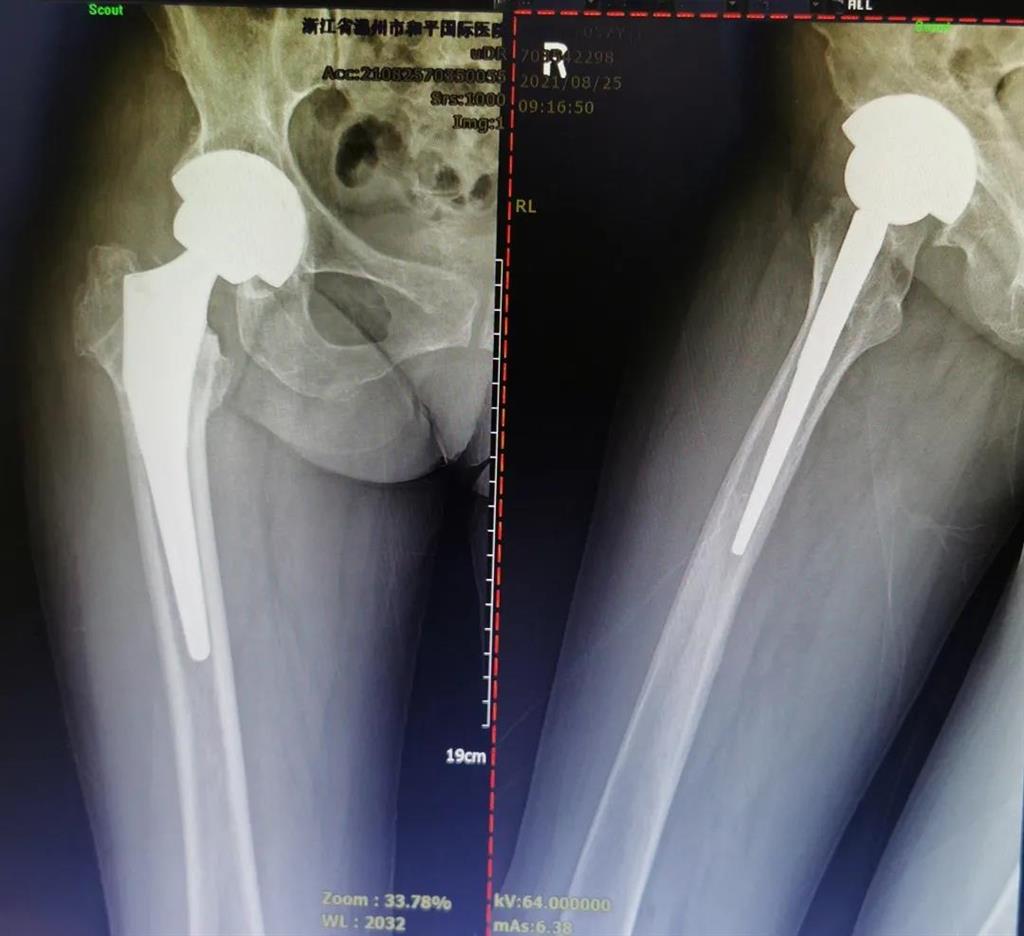

手術很成功!李女士術后第二天便可下地進行簡單的鍛煉了。

兩個月后,李女士的腿已與常人無異,苦纏2年有余的病痛,終于徹底消散。

(△做完“右股骨頸全髖關節(jié)置換術”后的影像)